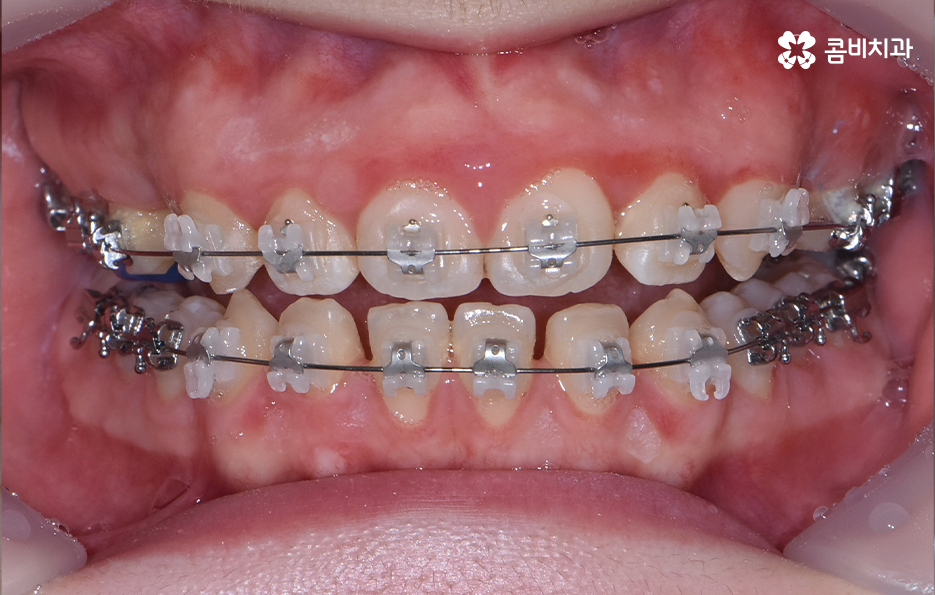

다음으로 교정 장치를 부착한 상태를 보시면 윗니는 양쪽의 치아 하나씩을 발치하였고 아랫니는 치아가 벌어져 있는 공간이 있기 때문에 발치 없이 교정을 진행했어요

앞니가 일반적인 경우보다 다소 돌출되어 있던 상태이기 때문에 앞니의 발치 교정을 통해 가지런한 치열 뿐 아니라 얼굴형이 변화하여 외모적인 개선도 기대할 수 있었어요. 치아교정의 목적에 있어서 치열 뿐 아니라 얼굴변화를 주된 목적으로 치과에 방문하는 경우도 많이 있는데요.

기본적으로 치아교정은 보다 가지런한 치열로 인해 자신감 있게 웃는 얼굴 만으로도 밝은 인상을 주는 효과가 있지만 치아의 이동이 많을수록 얼굴의 실질적 변화가 더 크기 때문에 치아교정에 대한 니즈가 치열 뿐 아니라 얼굴형에 더 초점을 두는 경우에는 발치 여부를 고려하는 경우도 종종 있어요